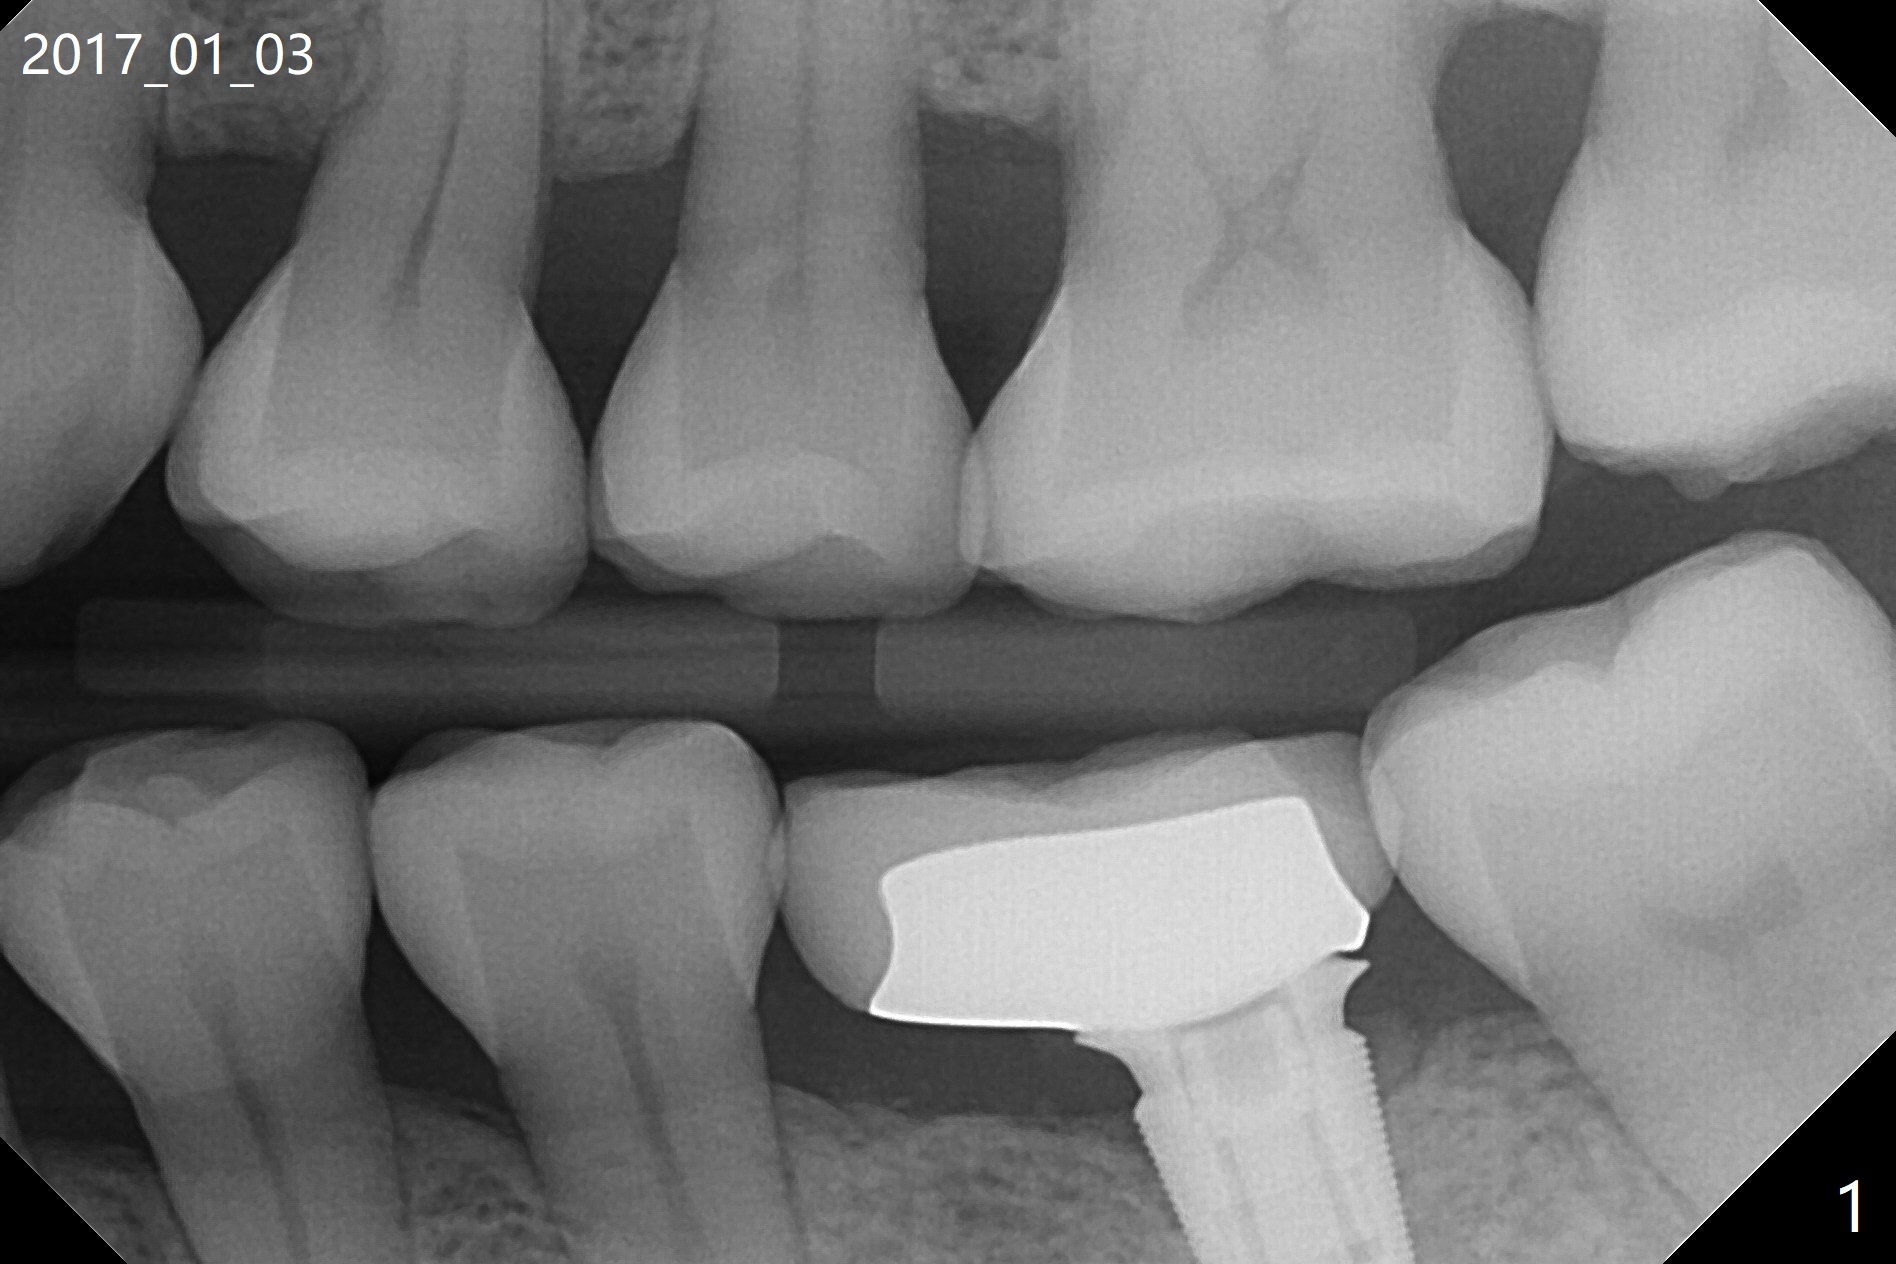

正畸帮助植牙 (互相):1. 缺牙间隙不太窄:先导板植牙后矫正;2.间隙很窄:顺序相反(徒手)